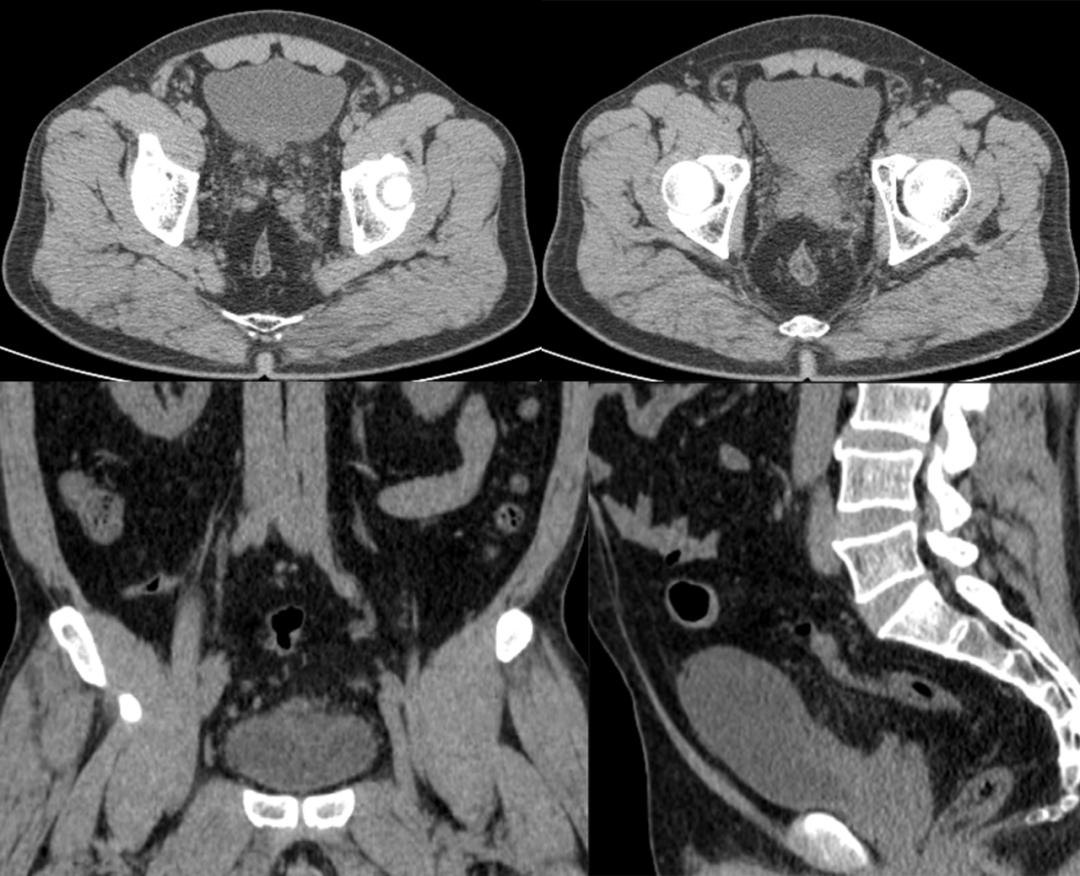

病例二

患者,男,49 岁,因尿频尿急 1 年,体检发现膀胱占位 5 天入院。

膀胱充盈尚可,后壁略增厚、毛糙,腔内未见明确异常密度影。前列腺体积不大,见结节状钙化影,双侧精囊腺略饱满,周围脂肪间隙浑浊。